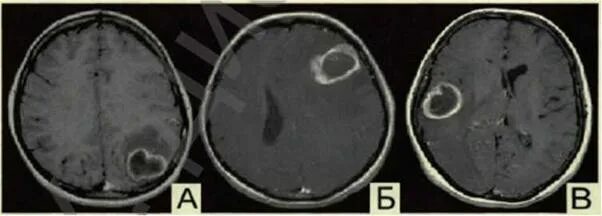

Метастазы головного мозга кт